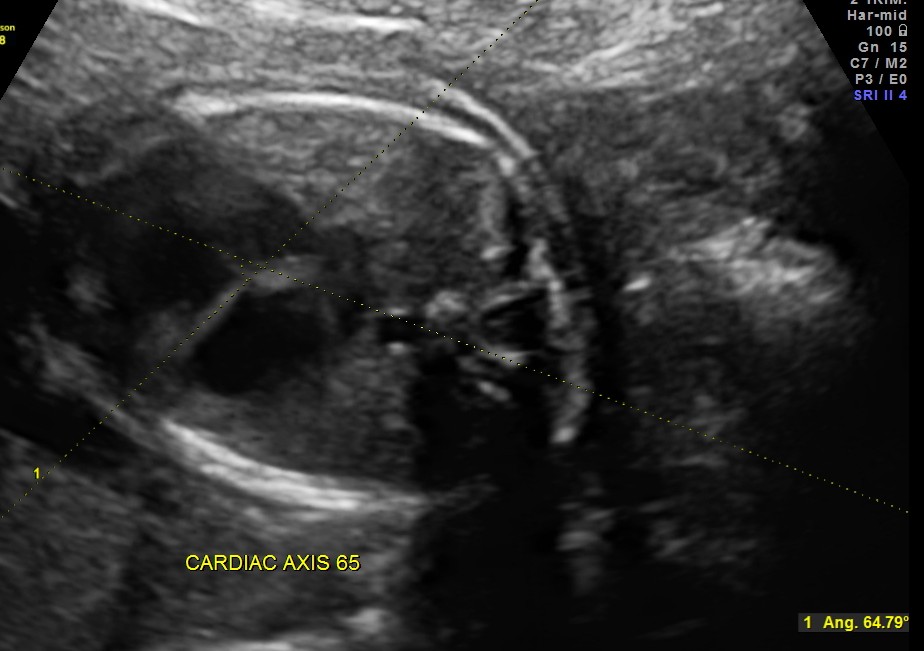

cardiac axis of less than 29 or more than 59 is considered abnormal ; in this fetus it was 65

5. Abnormal cardiac axis